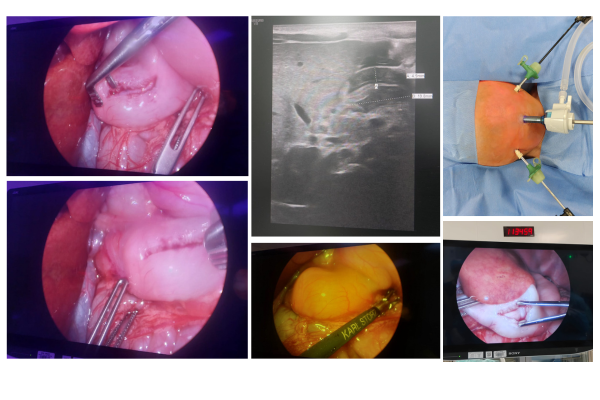

Laparoscopic Removal of Hemorrhagic Cyst from 40 Days Old Girl

Laparoscopic

Minimally invasive laparoscopic excision of a hemorrhagic ovarian cyst in a 40-day-old female neonate.